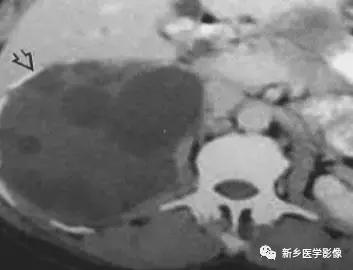

棘球蚴病

肾上腺囊性病变

主要包括合并钙化的感染性病变及肿瘤性病变,如: 肾上腺囊肿,肾上腺癌,嗜铬细胞瘤